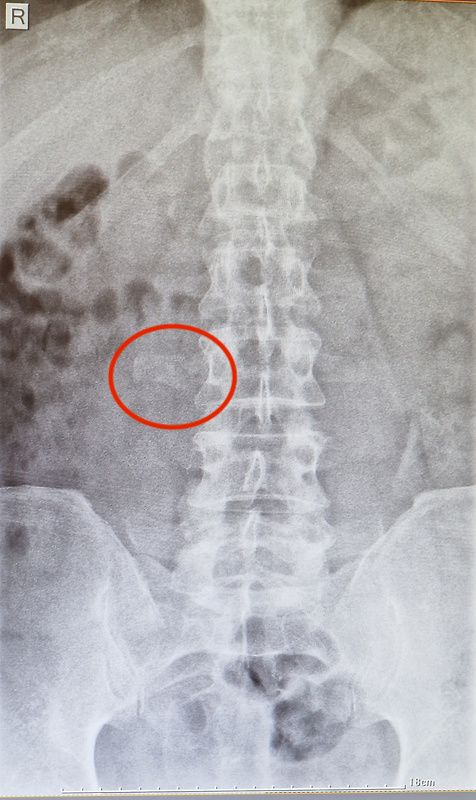

Die Polyklinik der größeren Stadt Izki liegt heute morgen direkt an unserer Route. Da legen wir doch mal einen kurzen Zwischenstopp ein, investieren zwanzig Minuten und fünf omanische Rial und knipsen ein bisserl in mich rein. Eine Untersuchung findet ansonsten eher nicht statt: Der Doc jagt mir ne Schmerzspritze in den Rücken, drückt mit ein paar chinesische Voltaren-Generica in die Hand und meint nach fünf Sekunden Röntgenbildblick nur: Alles OK.

Von einer deutschen Spezialistin bekomme ich allerdings trotz unmöglicher Qualität eines Handyfotos vom Krankenhaus-Bildschirm eine andere Diagnose. Und was meint ihr so? Sofort heimfliegen und unters Messer? Strandurlaub statt biken? Weiterfahren und Zähne zusammenbeißen?

Anyway... die Remote-Diagnose der Chef-Radiologin von daheim: Querfortsatz rechts bei LWK 3 auffällig, fraglich auch LWK 4. Konsequenz: Keine.

Nach kaum ner halben Stunde sind wir schon wieder aus aus dem Krankenhaus von Izki: Röntgenbild machen ging flott wie's Brezl backen: Wartezeiten keine, Kosten keine, Diagnose auch keine. Die kommt wenig später aus Deutschland: "Querfortsatz rechts bei LWK 3 auffällig, fraglich auch LWK 4". Könnte also schon was angeknaxt sein, sofern man das anhand von abfotografierten Krankenhaus-Bildschirmen noch beurteilen kann. Die Schmerzen passen jedenfalls irgendwie dazu. Egal, nix besonders ernstes, damit bin ich erst mal zufrieden. Ein MRT such ich mir jetzt aber nicht auch noch, irgendwann muss man die Kirche einfach im Dorf lassen. Der Milz geht's prima, hat sie mich gerade wissen lassen.